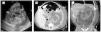

A su ingreso se reportó una creatinina sérica de 6.22 mg/dL, urea de 141 mg/dL, BUN 66 mg/dL, leucocitos de 26.2, hemoglobina de 7.44 g/dL. Se realizó un ultrasonido abdominal y una tomografía axial computada de abdomen, en los cuales se logró observar una fusión renal con presencia de ectasia de cavidades renales, y la pérdida de la continuidad del parénquima renal, así como la presencia de gran cantidad de líquido libre perirrenal sugestivo de un urinoma (Figura 2).

Figura 2. A) Ultrasonografía renal que muestra dilatación de cavidades. B) TAC corte axial en el que se observa périda de la continuidad del parénquima renal y líquido libro perirrenal. C) TAC corte coronal en el que se observa fusión renal con gran cantidad de líquido libre.